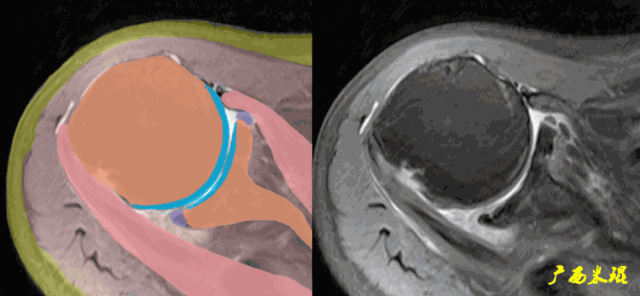

肩关节MRI检查扫描平面

3、轴位:平行于关节盂/垂直于盂肱关节,主要评估盂唇,同时兼顾肩胛下肌、冈下肌及小圆肌。

正常肩袖的MRI表现

各个序列肩袖均表现为均匀的低信号,是肌腱的延续。